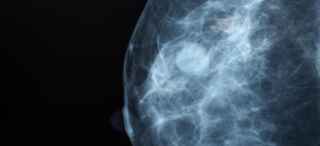

Imaging to show different densities in breast tissue

These X-ray scans show the four categories of breast density. The two images on the left are considered “not dense,” and the two on the right are considered “dense.”